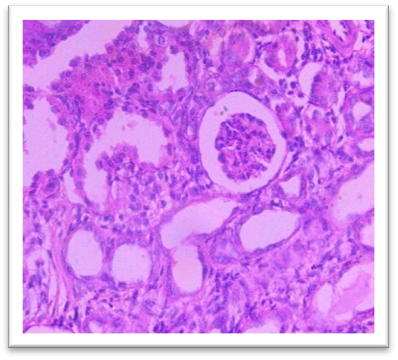

Histopathology

On day 42, rats were sacrificed for histopathological examination. Group I (Normal) and Group II (Lanthanum Carbonate only) showed normal kidney and liver architecture. Group III (Chronic Kidney Disease control) exhibited kidney damage, including crystals, congestion, haemorrhage, interstitial nephritis, and tubular dilatation. Group IV (Lanthanum Carbonate @150 mg/kg) showed moderate kidney fibrosis, mononuclear infiltration, and crystals. Group V (Lanthanum Carbonate @250 mg/kg) had mild fibrosis and sparse crystals. Group VI (Lanthanum Carbonate @500 mg/kg) showed minimal fibrosis and negligible crystals. Group VII (Lanthanum Carbonate @750 mg/kg) had minimal lesions with no crystals. Liver sections were normal in all groups. Histopathology studies revealed , The kidneys from a Chronic Kidney Disease (CKD) control rat (Group III) displayed significant macroscopic changes, including an increase in overall kidney size and the presence of multifocal, pinpoint, white granular raised lesions that were widely dispersed across the cortical surface. These observations are consistent with pathological alterations associated with CKD. Similar findings were reported by Yang et al. (2013) and Ali et al. (2015), who observed renal tissues exhibiting varying degrees of swelling and the presence of widespread white granular deposits on the cortical surfaces, consistent with the pathological features described in this study. Damment et al. (2011) observed significant changes in kidney architecture of Adenine induced Chronic Kidney Disease animals. The kidney from Group VII, treated with Lanthanum Carbonate @ 150mg/kg, 250mg/kg , 500mg/kg and 750 mg/kg body weight, demonstrated significant architectural improvement, along with a notable reduction in the number of crystalline deposits, indicating a substantial restoration of renal morphology and potential therapeutic efficacy at this dosage.

Fig. 20 Group IV Kidney shows moderate focal mononuclear cell infiltration with moderate fibrosis, and 3- 4 crystals under H & E 400 X

Fig. 21 Group V Kidney exhibits mild and focal interstitial fibrosis, sparse mononuclear cell infiltration, mild tubular dilatation, and 1- 2 crystals under H & E 400X.

Fig. 22 Group VI Kidney shows minimal focal fibrosis alongside mononuclear cell infiltration, crystals are nearly absent under 400X.

Fig. 23 Group VII Kidney shows very minimal or nearly absent lesions, including fibrosis and mononuclear cell infiltration, with crystals being absent under H & E 400X.